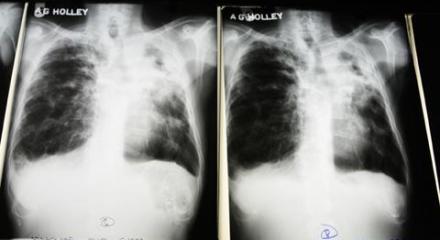

Hoa Kỳ tài trợ thiết bị chẩn đoán lao tiên tiến nhất cho Việt Nam Hình: AP Hình ảnh X-quang của bệnh nhân bị lao phổi Thông cáo báo chí của Ðại Sứ quán Mỹ tại Việt Nam ngày 6/2 cho biết Hoa Kỳ vừa trao tặng Chương trình Phòng chống Lao Quốc gia … Tiếp tục đọc